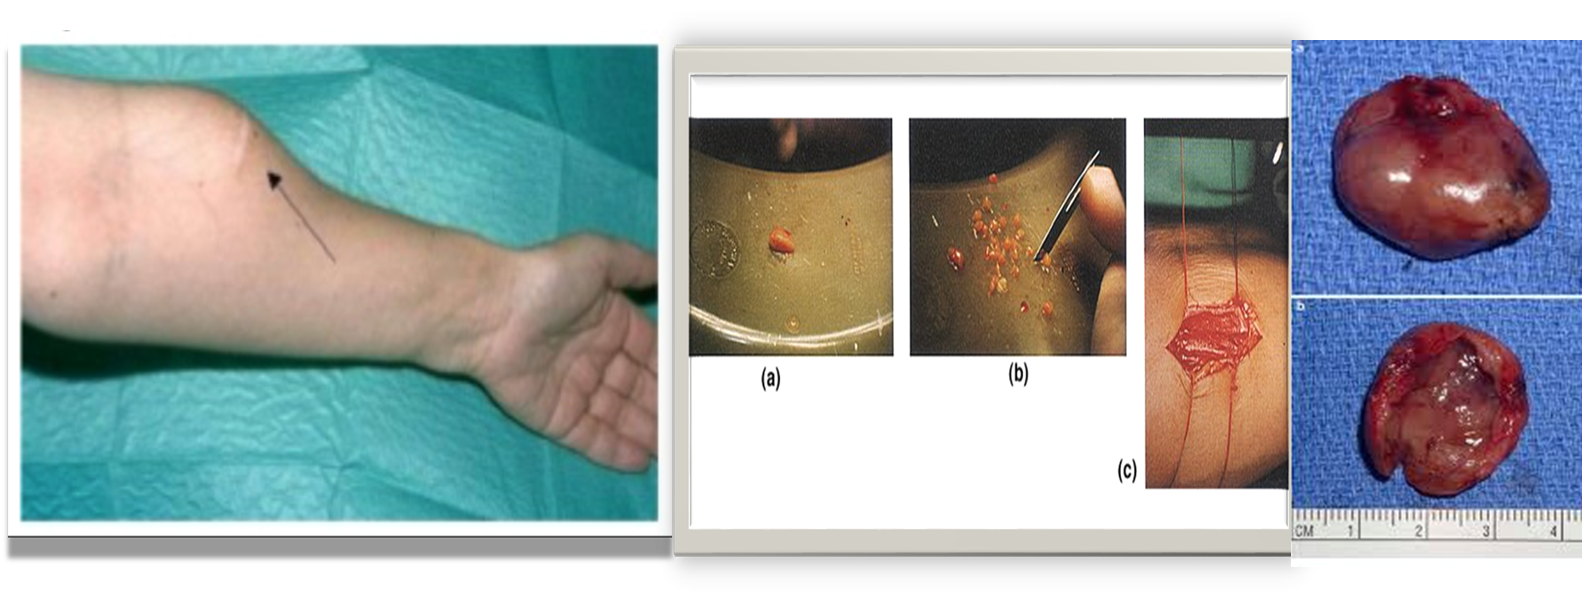

During surgery how will you confirm whether the tissue is parathyroid gland?

During surgery how will you confirm whether the tissue is parathyroid gland?

- Golden yellow color

- Put it in a cup of normal saline.

- Parathyroids usually sink but fat floats.

- Implant the parathyroid into the sternomastoid pocket or into the forearm

Complications of parathyroidectomy:

-

Post-op. bleeding

-

Hematoma:

- Pre tracheal (airway obstruction)

- pre- platysmal

-

Nerve injury

- 1-2% permanent:

- Recurrent laryngeal (hoarseness)

- Superior laryngeal (loss of high pitched sound)

- 1-2% permanent:

-

Hypocalcemia